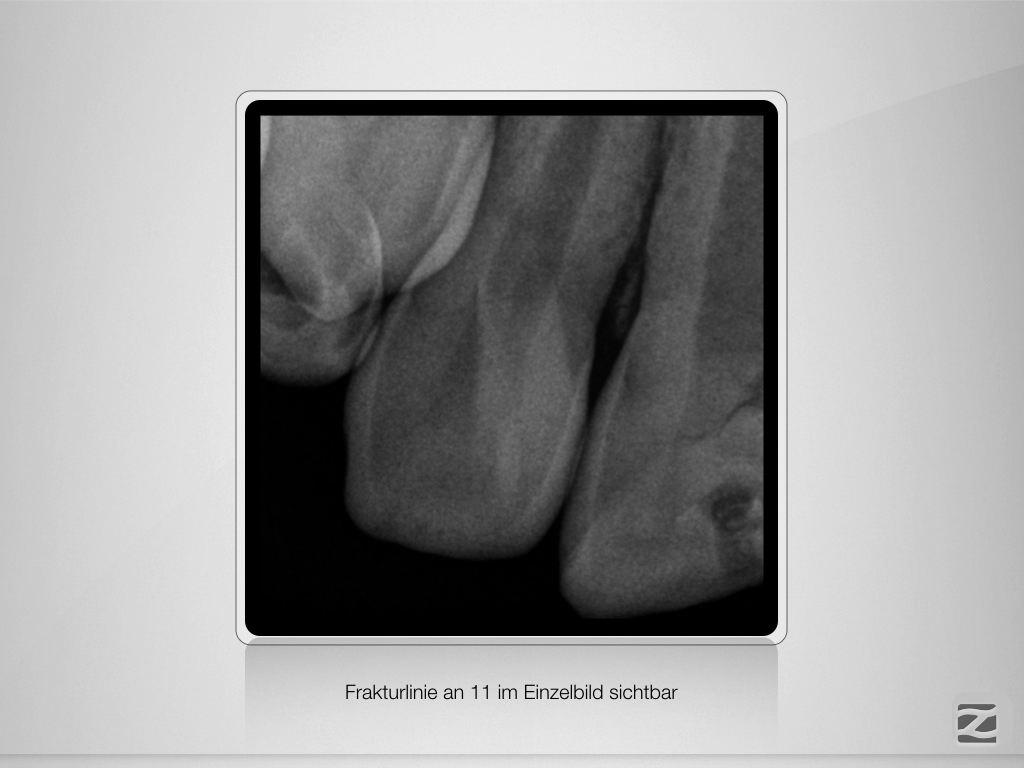

And the show goes on-Trauma, die Zweite.